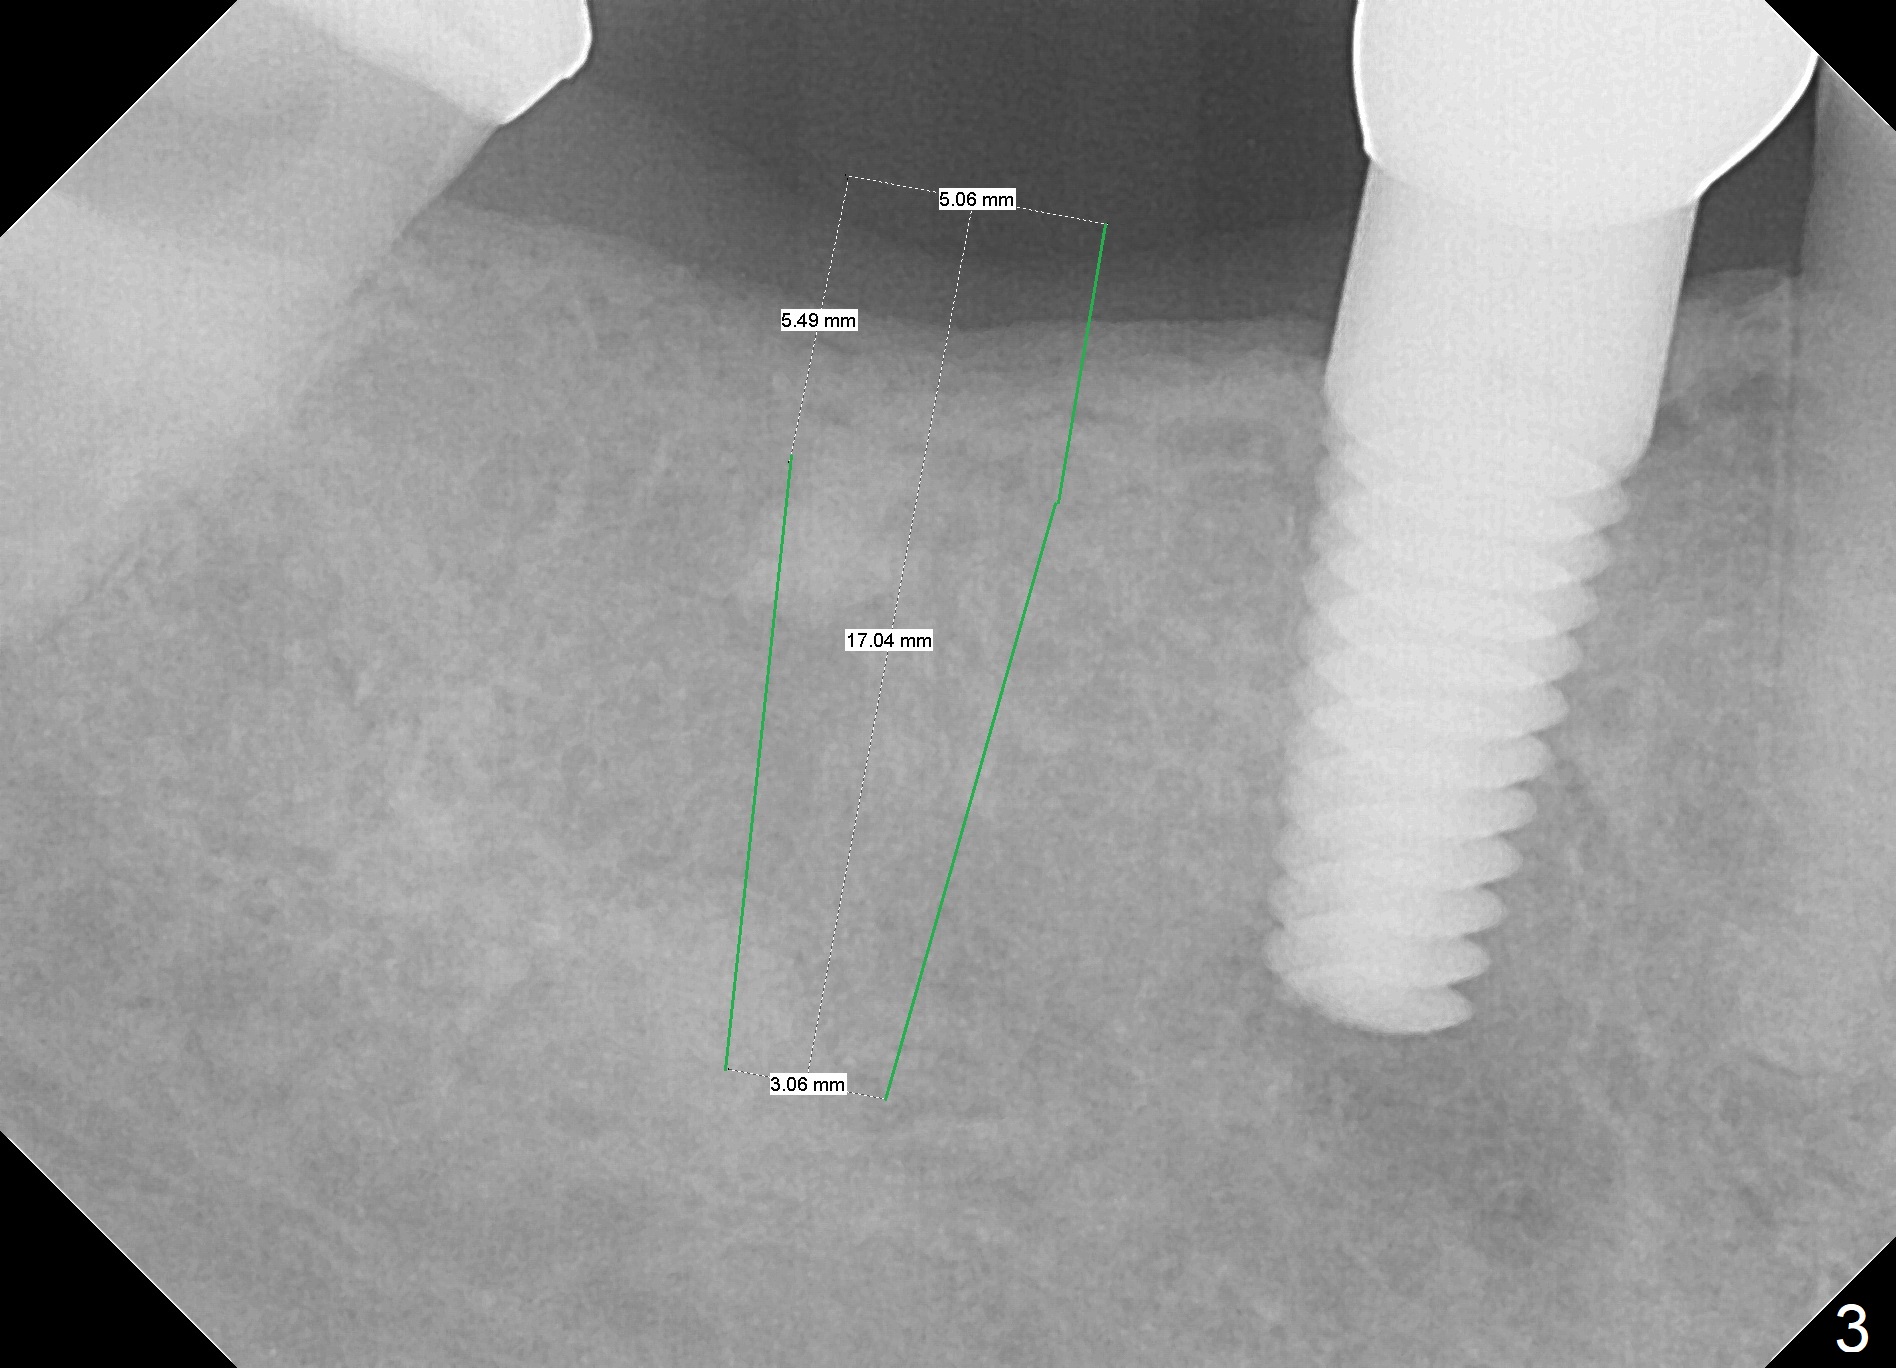

A 53-year-old woman returns for follow-up, requesting implant restoration at the sites of #30 and 31.  The edentulous space is ~14 mm mesiodistally (Fig.1), whereas a 6x17 mm implant was placed at #19 with ~13 mm space (Fig.2).  If the ridge at the LR molar region is wide enough buccolingually (3.5-5 mm Implant Positioners), place one implant (Fig.3, 4 mm Implant Spacer).  Otherwise, two of them will be placed (Fig.4).